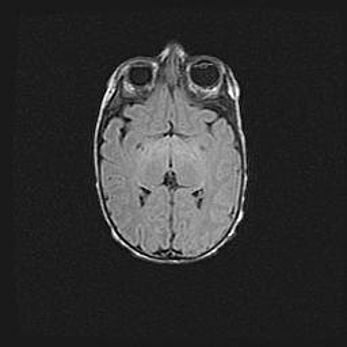

Сообщающаяся гидроцефалия. Кистозная энцефаломаляция головного мозга.

Возраст: 3 месяца 4 дня

Вес: 3100 г

Пол: женский

Окружность головы: 34 см

Срок гестации: 31 неделя

Кистозная энцефаломаляция головного мозга - одна из форм поражения головного мозга в детском возрасте. Характеризуется возникновением множественных и распространённых кист в коре, белом веществе и подкорковых образованиях головного мозга у плодов, новорождённых и детей раннего возраста. Развитие кистозной энцефаломаляции связано с внутриутробной асфиксией и гипотонией, родовой травмой, тромбозом синусов, пороками развития сосудов, инфекциями, сепсисом и другими причинами. Наиболее значимые инфекционные агенты: вирусы простого герпеса, цитомегалии, краснухи, токсоплазмы, энтеробактерии, золотистый стафилококк и другие.